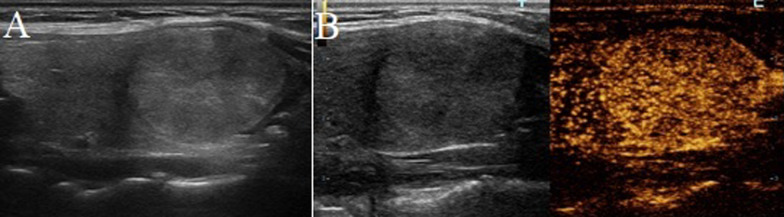

Fig. 2.

A follicular adenoma in a 53-year-old woman. A Greyscale ultrasound showed that there was a halo surrounding the thyroid nodule. B Contrast-enhanced ultrasound revealed regular high-enhancing ring (at the 24th second after the injection of contrast)